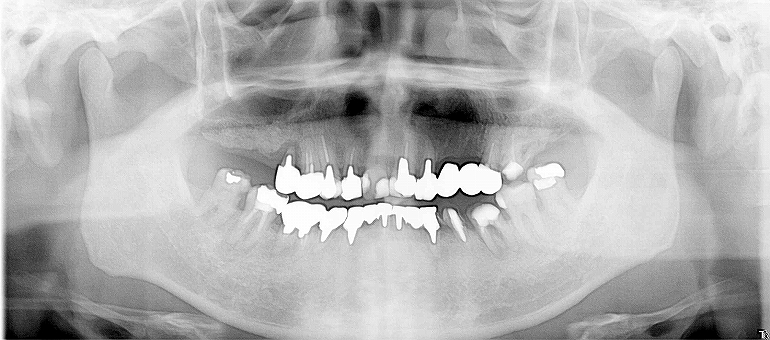

Vol.2

Before

奥歯で咬みにくい、

冠せがとれてしまった。

After

左上1本、右上3本、左下3本、右下1本、

計8本インプラント埋入。